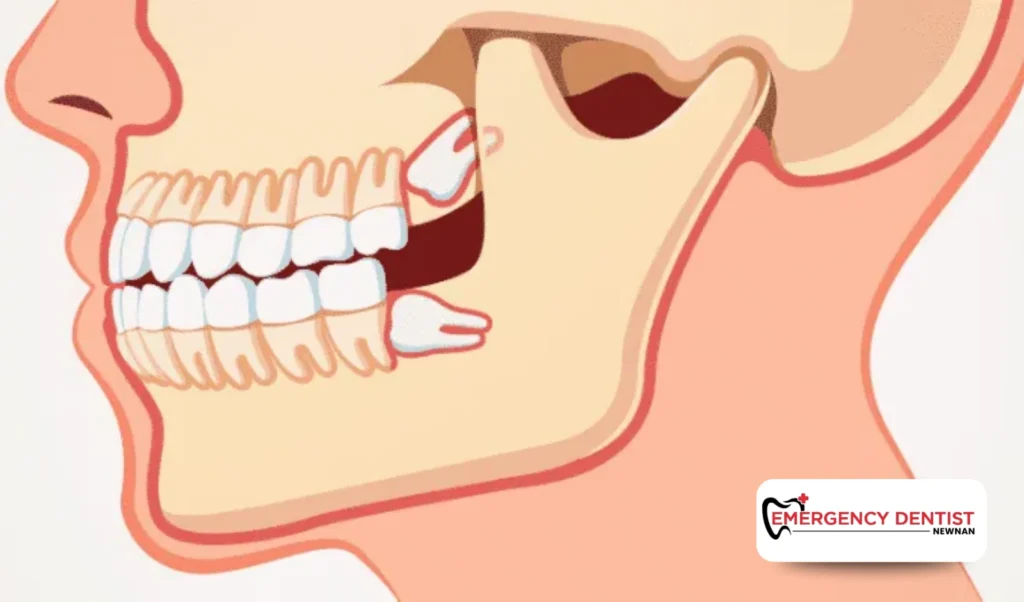

An impacted wisdom tooth does not fully emerge through the gums. It may grow sideways or press against nearby teeth. These cases often require oral surgery and additional planning.

Because more time and precision are involved, impacted cases often increase the average cost of a wisdom tooth removal. When patients ask, how much is a wisdom tooth extraction, the answer often depends on whether the tooth is fully erupted or impacted.